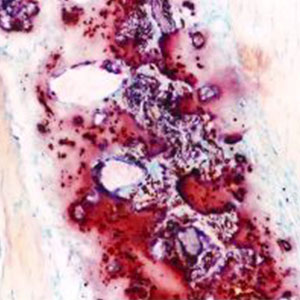

Rosso alizarina S

Per rosso d'alizarina s'intende un colorante di colore rosso estratto anticamente dalla radice della Rubia tinctorum.